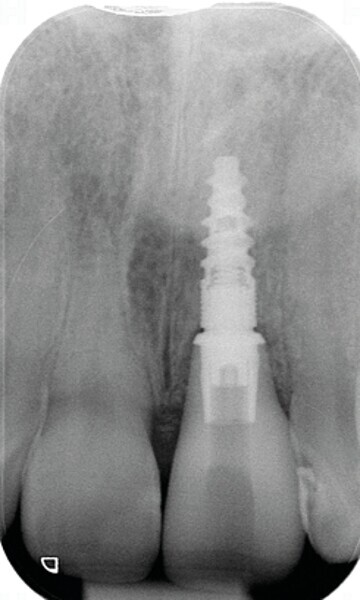

Fig. 22: Radiographie de l’implant et de la couronne in situ à cinq ans.

Lors du suivi a cinq ans, on ne peut que constater le résultat esthétique maintenu (Fig. 21). La radiographie montre un niveau osseux stable et une connexion étroite entre l’implant et le pilier (Fig. 22).